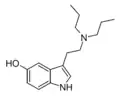

| 5-HO-DPT | artificial | 5-OH | CH2CH2CH3 | CH2CH2CH3 | 5-hydroxy-N,N-dipropyltryptamine | 36288-75-2 |